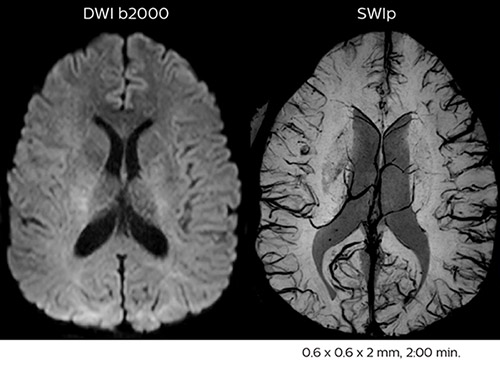

Acute right motor deficit and aphasia

In this patient with acute right motor deficit and aphasia, the b2000 diffusion weighted image is normal. The SWIp image demonstrates more prominent veins in the right hemisphere, which could reflect increased deoxyhemoglobin contents. Fast ASL shows low CBF regions in the left frontal lobe. A follow-up ASL after one hour demonstrates high CBF values in the same area. The final diagnosis was migraine with aura.